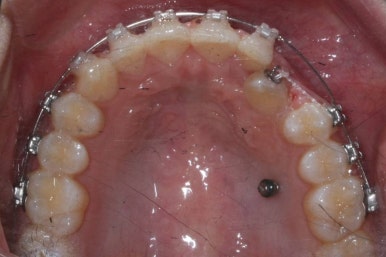

마무리 때의 사진입니다.

윗니만 부분교정하였지만 교합에도 이상 없이 매복되었던 송곳니는 매우 잘 위치를 잡았습니다.

송곳니 부위는 다시 틀어지지 않게 하기 위해 유지철사를 붙여주었습니다.

총 치료기간은 20개월 소요 되었습니다.

부산매복치아교정 상악 부분교정을 통해 매복치를 교정해준 이번 치료의 전후사진 비교입니다.

썩은 유치 대신 영구치 송곳니는 매우 자연스럽게 위치되었습니다. 아랫니는 교정하지 않았기 때문에 약간 삐뚠 느낌은 남아있지만 맞물림은 크게 문제가 없게 마무리 되었습니다.